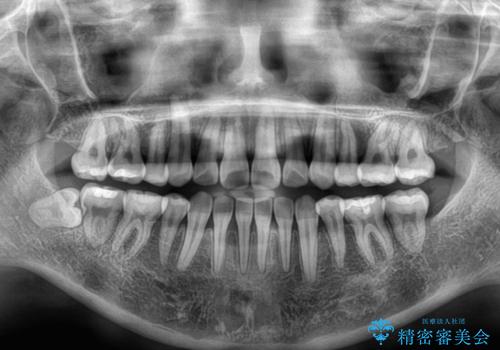

上下非接触の前歯 口元の突出感を改善する抜歯矯正

- 口元の突出感と上下前歯のズレを気にして来院された患者様です。

舌の突出癖により上下の前歯は非接触となっている状態でした。

舌のトレーニングを行わないと上下前歯の接触達成は困難であるため、トレーニングをしっかりと行っていただきながら、治療を進めて行くこととしました。

上下左右の第一小臼歯4本を抜歯し、ワイヤー装置にて矯正治療を行うこととしました。